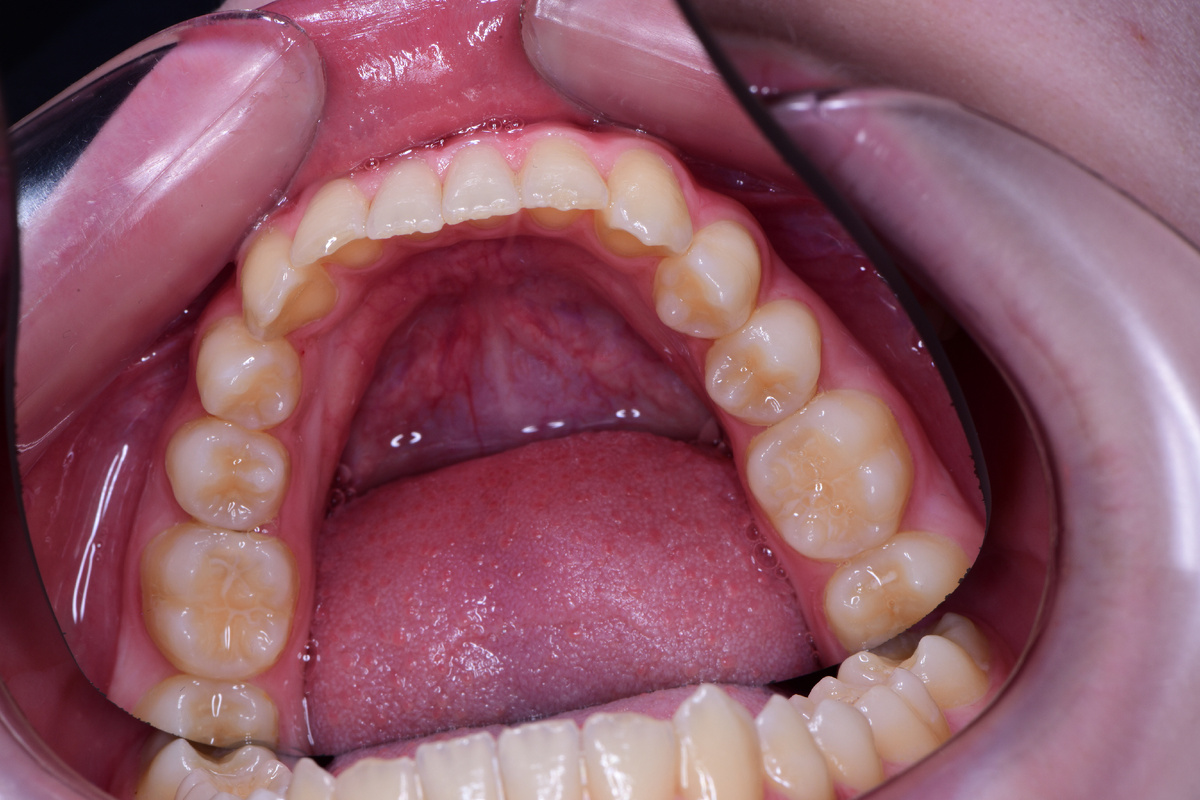

Первым делом мы провели диагностику, осмотрели зубы и десны пациентки. Десны выглядели воспаленными, покраснение и отек особенно заметны в области центральных резцов и клыков.

Причина — налет. Его много, и он лежит плотным слоем, особенно на клыках. Зубы выглядят матовыми, шероховатыми, без естественного блеска. Очевидно, что Маша недостаточно тщательно их чистит.

На верхней челюсти седьмые зубы пока только начинают появляться: виден лишь один бугорок. Зато шестые зубы тоже загерметизированы, что радует. Верхние «пятерки» еще молочные.

Верхняя челюсть: «семерки» только начинают прорезываться, пятые зубы еще молочные

Заметно, что клыки слегка приподняты над зубным рядом — это может быть поводом для установки брекет-системы в будущем. Но пока об этом думать еще рано, ведь не все постоянные зубы прорезались полностью.

Возможно, Маше потребуется ортодонтическое лечение